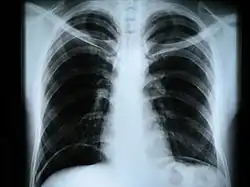

Рентгеногра́фия (от Рентген (фамилия учёного, открывшего этот вид электромагнитных волн) + греч. γράφω, пишу) — исследование внутренней структуры объектов, которые проецируются при помощи рентгеновских лучей на специальную плёнку или бумагу.

Наиболее часто термин относится к медицинскому неинвазивному исследованию, основанному на получении суммарного проекционного изображения анатомических структур организма посредством прохождения через них рентгеновских лучей и регистрации степени ослабления рентгеновского излучения.

Сейчас рентген грудной клетки часто используется для диагностики заболеваний, вызванных инфекциями лёгких. Однако этот метод оказался малоэффективен для обнаружения ранних стадий вирусных пневмоний, вызванных COVID-19.

В настоящее время рентгенография остаётся основным методом диагностики поражений костно-суставной системы. Важную роль играет при обследовании лёгких, особенно в качестве скринингового метода. Методы контрастной рентгенографии позволяют оценить состояние внутреннего рельефа полых органов, распространённость свищевых ходов и др.

- рентгенография грудной клетки — инфекционные, опухолевые и другие заболевания,